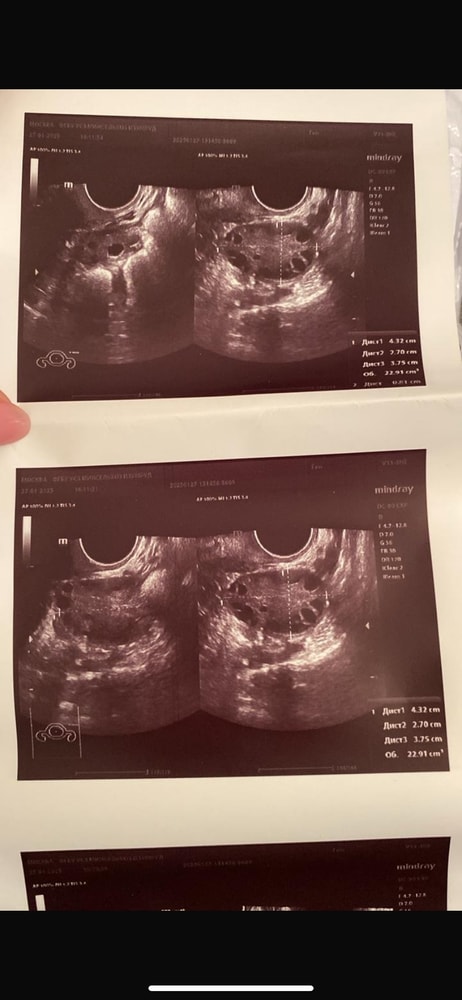

Ольга, РазмерыДлина: 46 мм, толщина: 34 мм, ширина: 49 мм, объем: 38.3 мл.Структура миометрияНе изменена.ЭндометрийТолщина эндометрия:8.0 мм.Полость матки:не деформирована, не расширена.Образования в проекции эндометрия:не выявлены.Правый яичник

Размеры: длина: 44 мм, толщина: 25 мм, ширина: 40 мм, объем: 22.9 мл; Фолликулы: не выявлены. Желтое тело: Есть. Размер 12 мм.

С множ. фолл. до 6 мм. лоцируется киста на ножке размером 33х30 мм.Левый яичник